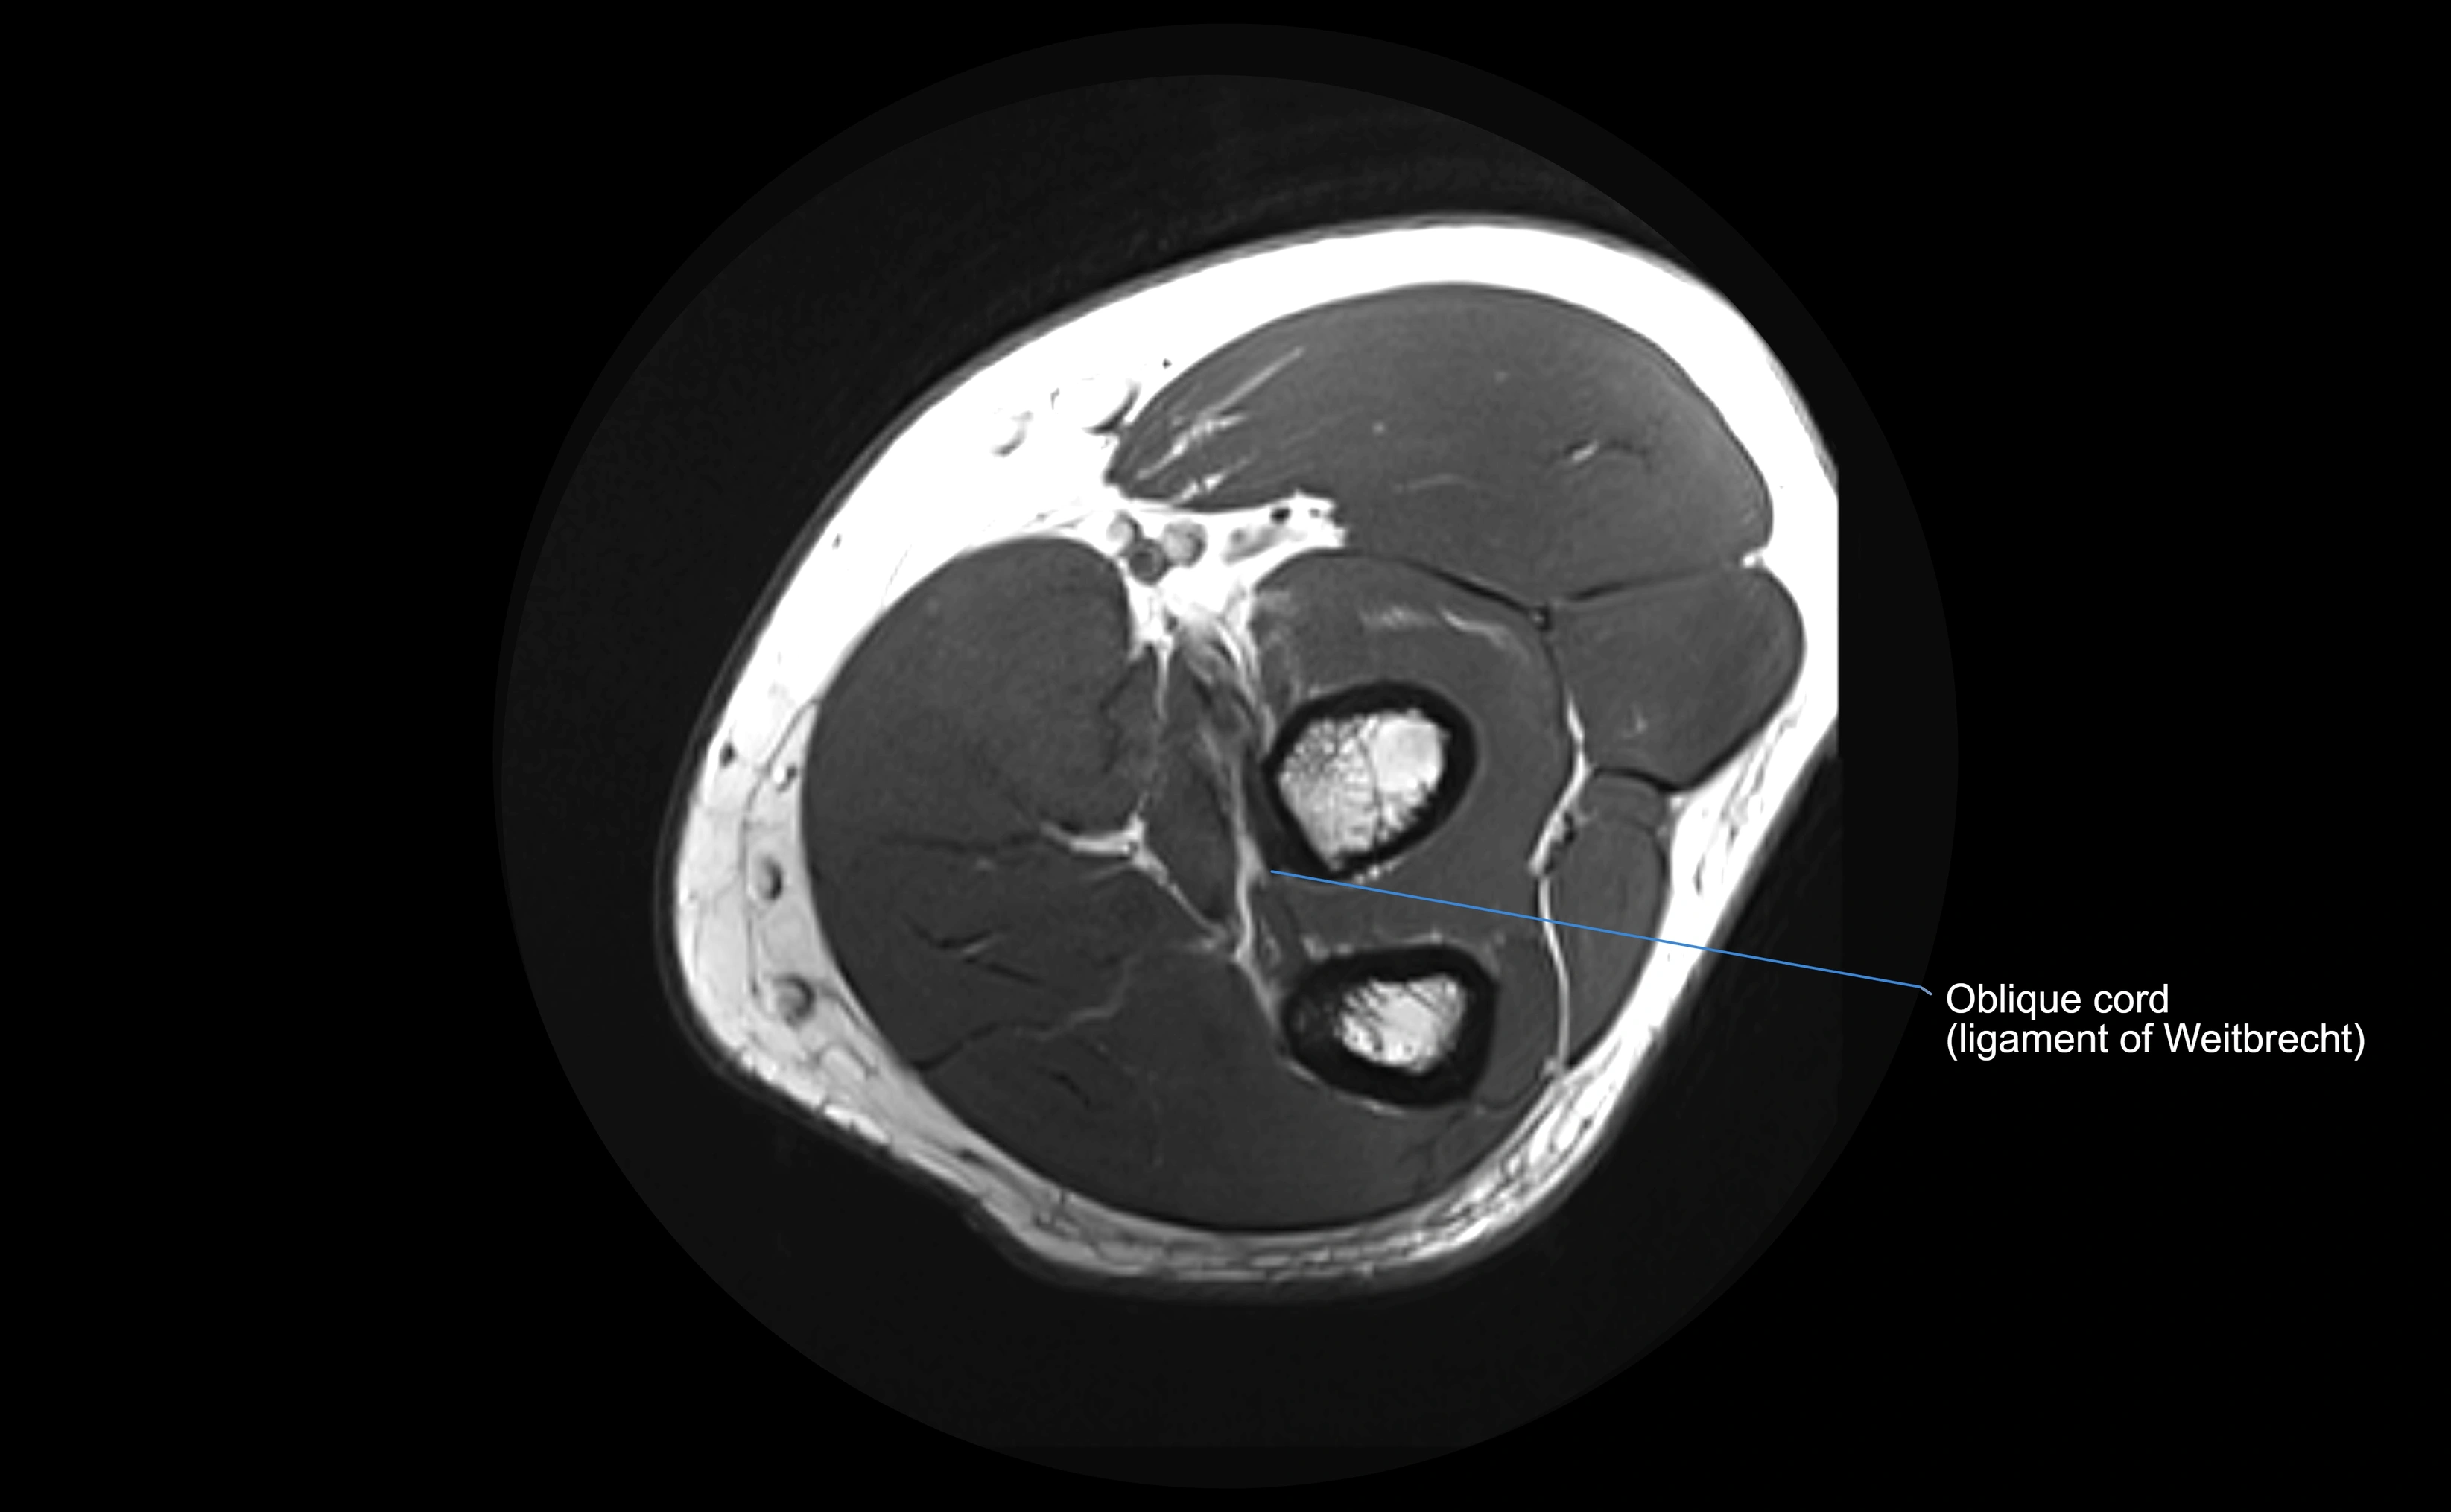

MRI images

image